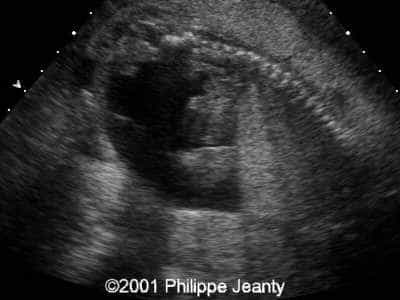

This 2nd trimester fetus has the following images (actually, these images remained unchanged for several weeks)

The findings are:

• very enlarged lungs on both sides

• inversion of the diaphragm that is convex towards the abdomen

• small compressed heart

• ascites but no generalized hydrops (no skin thickening for instance)

A much more common diagnosis for a bilateral echogenic lung associated with microcardia and ascites (Budd-Chiari phenomenon) is Larynx, atresia or as reported by several the CHAOS syndrome which stands for Congenital High Airway Obstruction Syndrome (which is typically laryngeal or tracheal atresia). This is the diagnosis that was indeed suspected in this fetus.